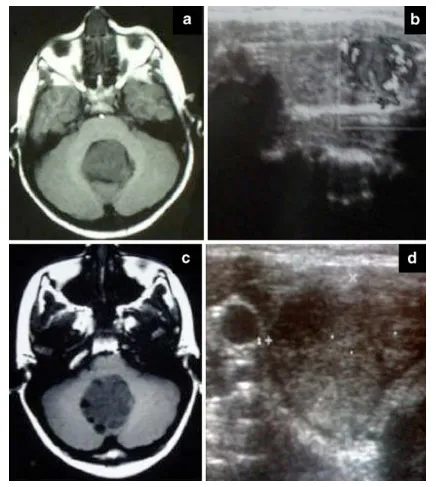

图1a–c 为我们两位患者的术前T1加权MRI图像,显示延伸至第四脑室的中线占位性病变。b–d 为术前甲状腺超声检查图像,显示两位患者甲状腺右叶均存在低回声肿块。